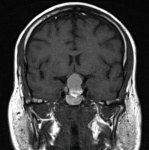

Neuroimaging

The pituitary gland is best seen on coronal sections and normally enhances with contrast. As with any radiographic study, detailed communication with the radiologist/neuroradiologist will help guide the appropriate study as well as careful examination of the images. Pituitary or sella sequence magnetic resonance imaging (MRI) with and without contrast is the study of choice for most sellar and parasellar lesions, but high-resolution CTs with fine cuts (1.5-3 mm) have also been shown to be very helpful in the differential diagnosis especially if calcification is seen (e.g., craniopharyngioma or meningioma).[2]

Magnetic Resonance Imaging (MRI)

Microadenomas are best seen on unenhanced T1-weighted coronal or sagittal scans. They are seen as hypointense areas within the substance of the relatively hyperintense pituitary gland. With gadolinium contrast these lesions will remain less intense compared to the normal gland and will enhance late. On T2-weighted images, the adenoma is more indistinct, as it appears isointense or only slightly hyperintense in comparison with the surrounding gland.[40]

Macroadenomas are more obviously seen, as they extend beyond the anatomical borders of the sella. The homogeneity of the images suggests the relative solidity of the tumor. Nonsolid tumors (macrocystic and macrohemorrhagic) have been suggested to be more effectively managed with transsphenoidal hypophysectomy in comparison with solid tumors.[41]